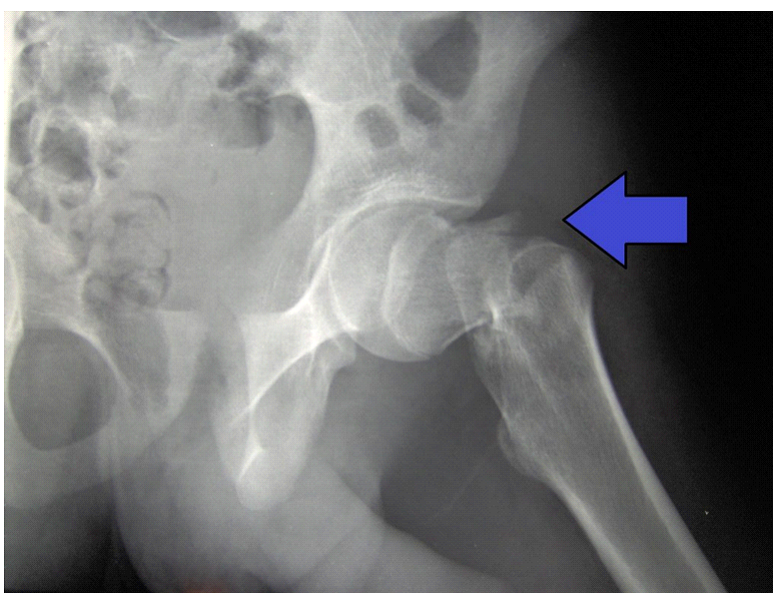

Actualmente tenemos la posibilidad de mejorar la resistencia del hueso y prevenir las fracturas de las personas mayores. Lo hacemos con una simple inyección dentro del hueso de una sustancia cálcica especial (OSSURE LOEP) que le fortalece y estimula la regeneración del hueso propio. Este efecto es inmediato, a diferencia de la medicación, que tarda meses o años en conseguirlo.

El producto OSSURETM LOEP se INYECTA EN EL HUESO para RELLENAR Y formar hueso nuevo en áreas del esqueleto OSTEOPOROTICO QUE PRESENTA MULTIPLES PEQUEÑAS CAVIDADES VACIAS. ESTE material biorreabsorbible, Y osteoconductor ESTÁ HECHO A BASE DE CALCIO. El procedimiento de mejora ósea local es un procedimiento mínimamente invasivo. Se inyecta en sitios preparados quirúrgicamente OSSURE donde se endurece, se reabsorbe y se reemplaza con hueso nuevo.

Ejemplos de algunos casos ya operados